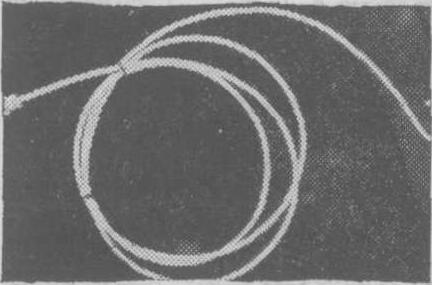

图3 猪尾状造影心导管

(2) 选择性左心室和主动脉造影: 选择性左心室造影可通过经胸壁穿刺左心室法、穿刺心房间隔左心导管检查法或经动脉逆行左心导管检查法(见“左心导管检查” 条) 等来施行。其中以后者最为安全可靠,并可同时施行选择性主动脉造影,尤以经皮肤穿刺股动脉法送入猪尾状左心室造影心导管最为简便(图3)。

术前准备除需作碘造影剂的过敏试验外,与经动脉逆行左心导管检查同。如从上肢动脉或颈外动脉送入心导管则以选用右侧较易送到升主动脉,如从下肢动脉送入心导管则选用左、右两侧股动脉均可。心导管顶端进入升主动脉后有时通过主动脉瓣有困难,此时顶端一段弯成圆圈状的心导管例如猪尾状心导管则较易送入。猪尾状心导管一般通过经皮股动脉穿刺法送入,当其套在导引钢丝外时,其顶端弯成圆圈部分即变直,便于经动脉穿刺口进入,撤出导引钢丝则顶端恢复圆圈状。当顶端经过主动脉瓣进入左心室有困难时,还可将导引钢丝再置入其管腔,但不到达顶端圆圈状部分,这样心导管的硬度加强而顶端仍呈圆圈状,更易于送入左心室。注射造影剂时心导管顶端的位置宜游离在心室腔中,并离二尖瓣较远,以避免造影剂注入心肌发生危险或反流入左心房,人为地造成二尖瓣关闭不全的假象。摄片取右或左前斜位投照。